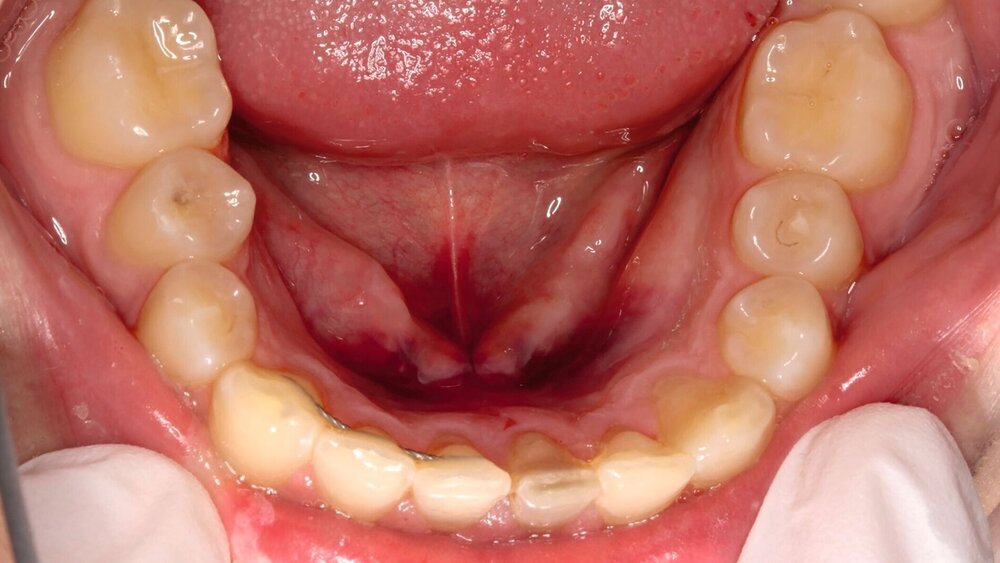

Zusätzlich zeigten sich ein dunkel-bläuliches Hämatom sublingual in Regio 32 bis 42 und ein korrespondierendes Hämatom im Vestibulum zwischen den Zähnen 31 und 41 (Abbildungen 1 und 2). Beide schienen mit der extraoralen Kinnwunde zu korrelieren und waren auf Palpation schmerzhaft. Es konnten keine Stufen ertastet und keine Krepitation wahrgenommen werden (Flowcharts Abbildungen 13 und 14).